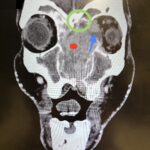

Sinonasal carcinoma is a rare malignancy that often presents with nonspecific symptoms, making early diagnosis challenging. Delayed recognition can lead to disease progression and worse outcomes. This case report emphasizes the importance of early identification, prompt imaging, and multidisciplinary management. A 73-year-old male with a history of anemia and hypertension presented with progressive facial swelling, 20-pound weight loss, and vision loss in the left eye over two months. Initially misdiagnosed with bacterial sinusitis, his symptoms persisted. Examination revealed a proptotic left eye and a large obstructive nasal mass. Computed tomography (CT) and MRI (magnetic resonance imaging) demonstrated a destructive sinonasal mass with skull base and intracranial extension. A biopsy confirmed sinonasal carcinoma, and the patient was started on chemoradiation therapy due to the inoperability of the tumor.

This case underscores the importance of recognizing red flag symptoms such as persistent facial swelling and neurological deficits. Multimodal imaging played a critical role in diagnosis. The literature suggests sinonasal carcinoma is often diagnosed late, reinforcing the need for early suspicion and specialist referral. Sinonasal carcinoma should be considered in patients with persistent facial or nasal symptoms. Timely imaging, biopsy, and interdisciplinary care are essential for optimizing outcomes.